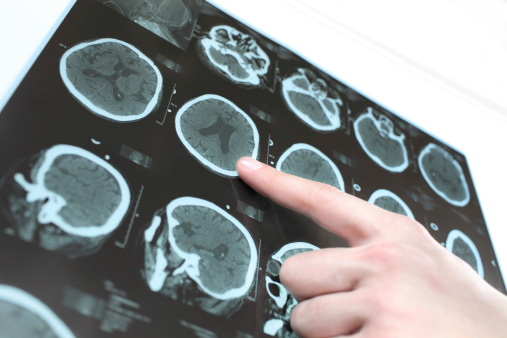

This past week was the National Alcohol Screening Day, which is important as it raises awareness around the harmful effects of alcohol consumption, including Parkinson’s disease, heart risk, and eyesight and vision problems. Here at Bel Marra Health we want to keep you in the know, so we put together this roundup of health articles ...click here to read more